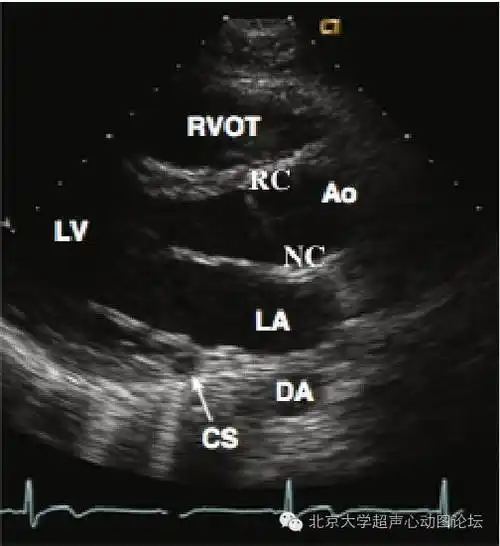

【零基础学心超,一天一图一讲解001】之胸骨旁左心室长轴切面